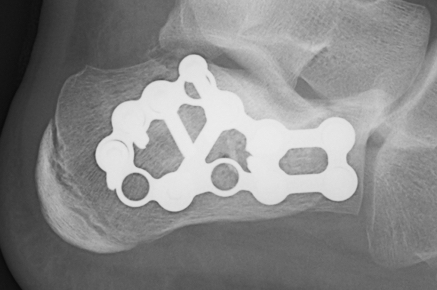

ORIF lateral plate using extensile lateral approach

Depuy Synthes calcaneal locking plates PDF

Anatomical contoured locking plate